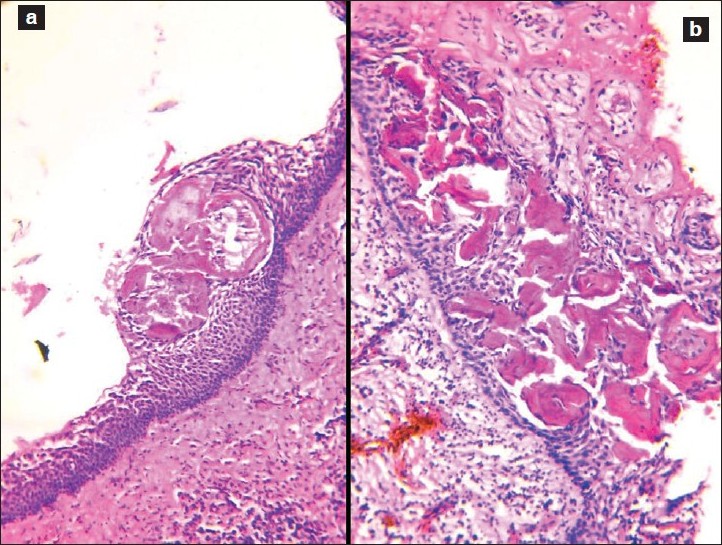

A cyst was removed along with an unerupted third molar tooth. The pathologist reported a fibrous capsule that was myxoid in places and that was lined by a thin layer of squamous and cuboidal epithelium. The cyst originated from the amelocemental junction.

When a tooth fails to erupt properly, sometimes a cyst can form around it. This cyst is called a dentigerous cyst. It is characterized by a fibrous capsule, which is like a protective layer, and it is lined by stratified squamous epithelium, which is a type of tissue that forms the outer layer of the cyst.

Histologically, dentigerous cysts may show various features such as the thickness of the epithelial lining or the presence of inflammation or keratinization. However, these features are not unique to dentigerous cysts and can also be seen in other types of cysts.